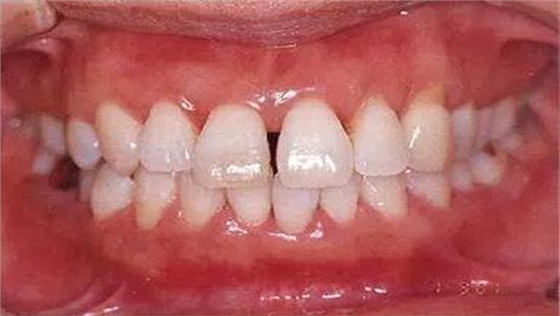

●33歲男性 侵襲性牙周炎廣泛型口腔內(nèi)照片

33歲男性,吸煙(1天10根,12年吸煙史)。菌斑控制狀況不好,牙周探診全頜牙周袋深5~10mm之外,全頜性牙周袋出血,部分牙周袋有排膿現(xiàn)象。X片可觀察到全頜性重度骨吸收。通過以上檢查可診斷出該患者為侵襲性牙周炎廣泛型。視診可知牙齦雖然有炎癥,但沒有出現(xiàn)嚴(yán)重浮腫,沒有大量牙結(jié)石沉積。